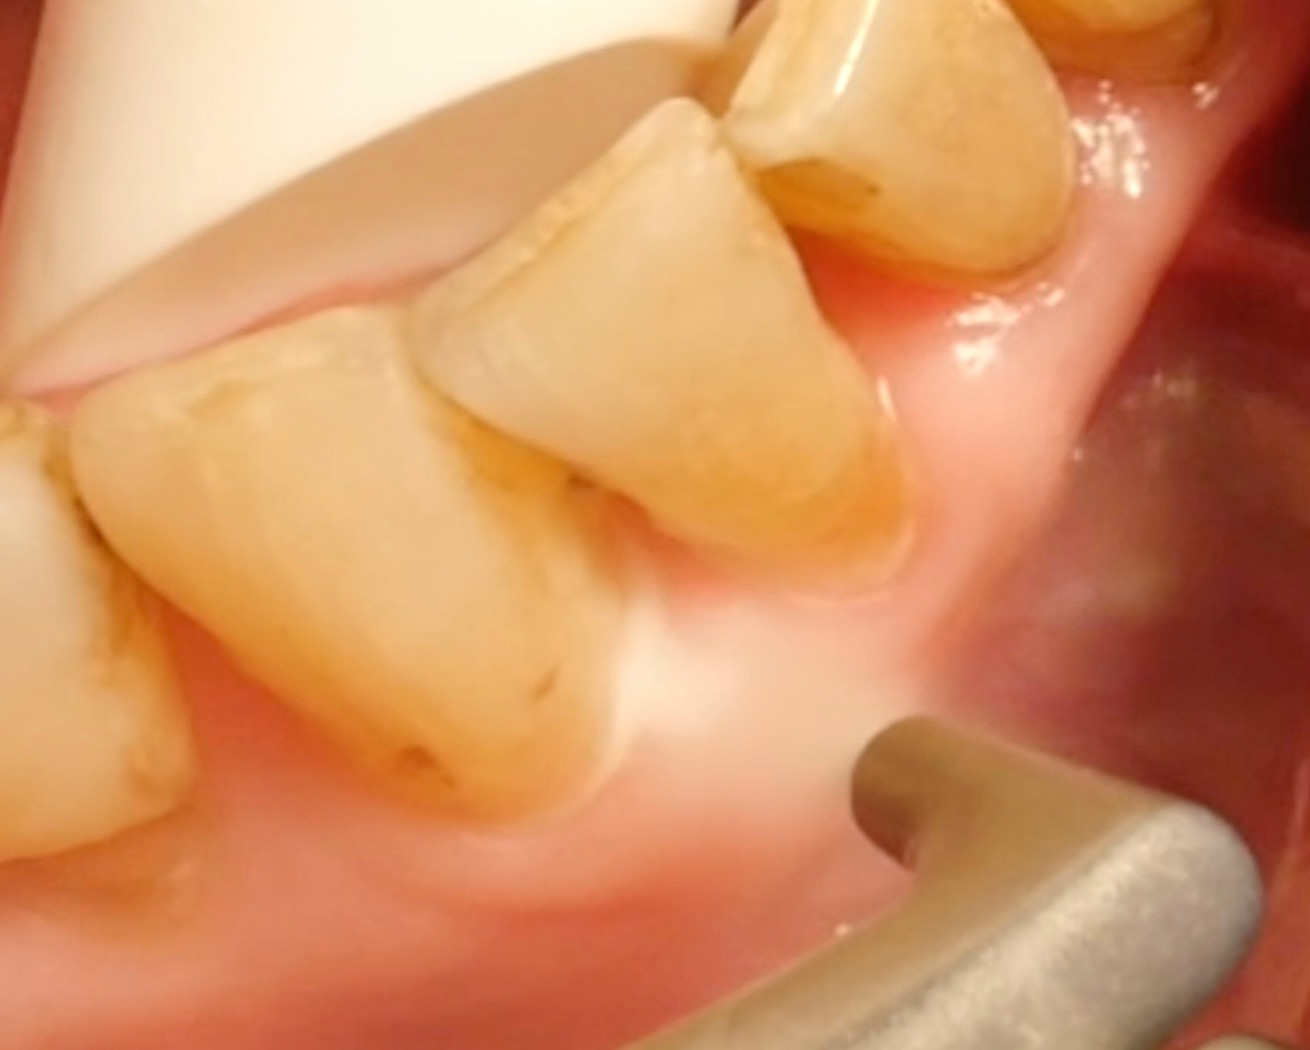

Air polishing devices have become a firmly established part of periodontal treatment in recent years. But how efficient are they? What applications do they have? What should be considered when using them?

• Supra- and subgingival use of glycine-based powders is safe and effective.

• In contrast, powders containing sodium bicarbonate should not be used in periodontal treatment, because these powders can cause considerable damage to exposed cementum and dentine and to the gums.

• For pocket probing depths of ≤ 4 mm and of 5–9 mm, removing biofilm with an air polisher is more effective and quicker than conventional methods; however, the clinical outcome is comparable, and no method is clearly superior.

• However, it is essential to note that air-polishing devices cannot ablate deposits of tartar and calculus; here, a combination of (ultra)sonic devices and/or hand instruments must be used.